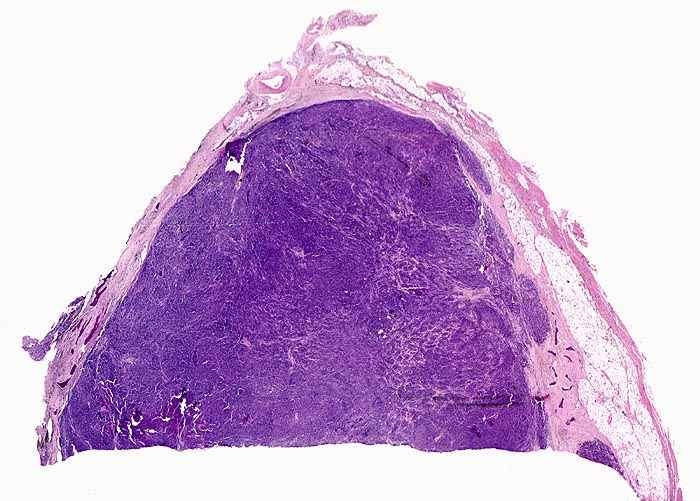

Plasmazellmyelom

Knochenmark, Wirbelkörper

Von schmalen bindegewebigen Septen durchzogene solide basophile Tumormasse ohne erkennbare Markstrukturen. Im Randbereich sind einzelne Knochenbälkchen erkennbar.

Notfalleinweisung wegen umschriebenen Thoraxschmerzen ohne adäquates Trauma. Im Röntgenbild Nachweis multipler Frakturen der Wirbelsäule und der Rippen bei grobsträhniger Osteoporose. In der Serumelektrophorese Nachweis einer Paraproteinämie.

Diagnosesicherung: Immunhistologischer Nachweis von monoklonalem Immunglobulin (IgG oder IgA und kappa- oder lambda-Leichtketten in einem Verhältnis von >1:16 bzw. >16:1). Klinisch entsprechender Nachweis einer Paraproteinämie oder Proteinurie (Bence-Jones Protein = monoklonale freie Leichtketten).